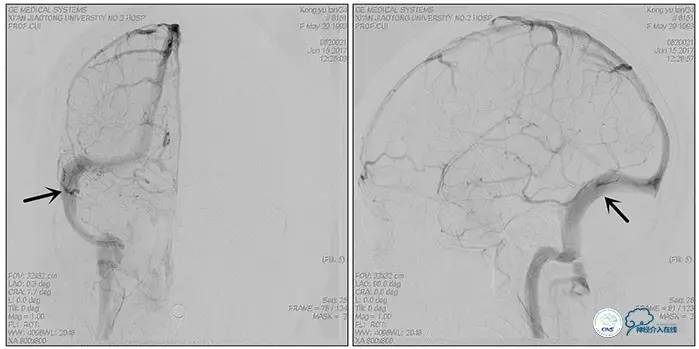

右侧ICA造影正侧位

右侧ICA造影斜位

右侧ICA正侧位

右侧ICA斜位

静脉淤滞

左侧ICA斜位

左侧VA正斜位

诊断:1、右侧横窦、乙状窦狭窄;2、继发性癫痫;3、双侧视神经萎缩;4、脑室腹腔分流术后;5、椎管内占位切除术后。

诊疗方案:为挽救视力,确定支架成形术效果,急诊行右侧横窦乙状窦狭窄球囊扩张术(6mm×20mm,Ever Cross )。

术中测压

远端压力:530mmH2O

近端压力:120mmH2O

术中造影

术后造影

狭窄较前有改善